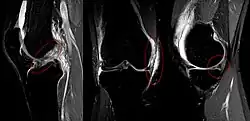

![]() | |

The unhappy triad, also known as a blown knee among other names, is an injury to the anterior cruciate ligament, medial collateral ligament, and meniscus. Analysis during the 1990s indicated that this 'classic' O'Donoghue triad is actually an unusual clinical entity among athletes with knee injuries. Some authors mistakenly believe that in this type of injury, "combined anterior cruciate and medial collateral ligament (ACL- MCL) disruptions that were incurred during athletic endeavors" always present with concomitant medial meniscus injury. However, the 1990 analysis showed that lateral meniscus tears are more common than medial meniscus tears in conjunction with sprains of the ACL.[1]